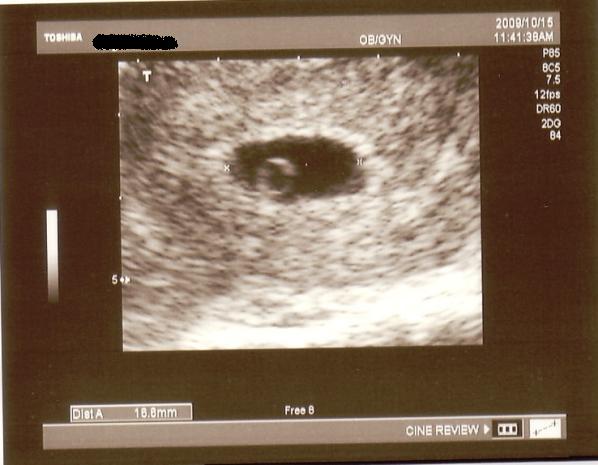

Ma voltam szülásznőmnél, tök tipikus, hogy bementünk az UHra, na ki van bent doki??? Hát eprsze, hogy az enyém.

De rohant szerencsére, mert műteni ment.

Minden rendben lurkóval, valóban fejvégű, 2100 gr. Kissé nagyobb lesz, mint Bátyja. Megint szóba jött a doki-dolog, hát eléggé meglepődött, amikor mondtam, hogy valószínűleg a dokim nézte el a gyerek fekvését (26. héten faros volt, utána éreztem egy fordulást -egyértelműen-, 30. héten mégis farosnak mondta a doki, azaóta nem éreztem fordulást és most viszont fejvégű (meg ugye előző héten is az volt) ergo szerintem a doki nézte el. No a lényeg, hogy megint beszéltünk erről, de mondtam Neki, hogy már nem akarok nagyon ugrálni... Amúgy a szülésznőmnek mondta, hogy majd együtt szülnek és hogy én leszek az... jééé emlékszik... És lenne mégegy téma ezzel kapcsolatban, de azt nem merem itt nyíltan...